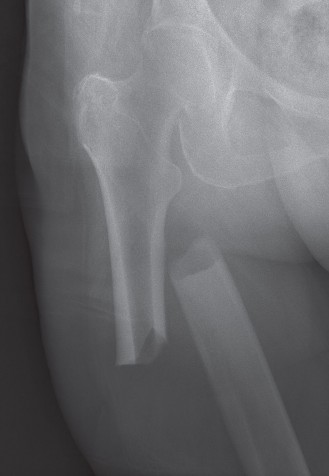

Subtrochanteric femur fractures, often referred to as the "silent threat" due to their challenging nature and potential for significant morbidity and mortality, represent a distinct and complex subset of proximal femoral injuries. Defined anatomically as fractures occurring within the region extending from the lesser trochanter distally approximately 5 cm along the femoral shaft, these injuries are characterized by their location in a highly stressed segment of bone, surrounded by powerful musculature. This unique anatomical and biomechanical environment predisposes them to high rates of comminution, displacement, and persistent deforming forces, making their management a formidable task for the orthopedic surgeon.

Epidemiologically, subtrochanteric fractures exhibit a bimodal distribution. In younger, active individuals, they typically result from high-energy trauma, such as motor vehicle collisions or falls from significant heights. These fractures are often severe, comminuted, and may be associated with polytrauma, requiring meticulous assessment for concomitant injuries. In contrast, the majority of subtrochanteric fractures are observed in the elderly population, frequently as a result of low-energy falls in patients with underlying osteoporosis or other metabolic bone diseases. This demographic often presents with multiple medical comorbidities, complicating both surgical and anesthetic management. A notable and increasingly recognized subset in this older population comprises atypical femoral fractures (AFFs), often associated with prolonged bisphosphonate use, which present with characteristic radiographic features and unique healing challenges.

The subtrochanteric zone is classically defined as the segment of the femur extending from the inferior border of the lesser trochanter distally for approximately 5 cm. This area is distinguished by its dense cortical bone, particularly along the linea aspera, providing significant structural integrity. However, it is also a region of high stress concentration, making it vulnerable to fracture under both traumatic and cyclic loading.